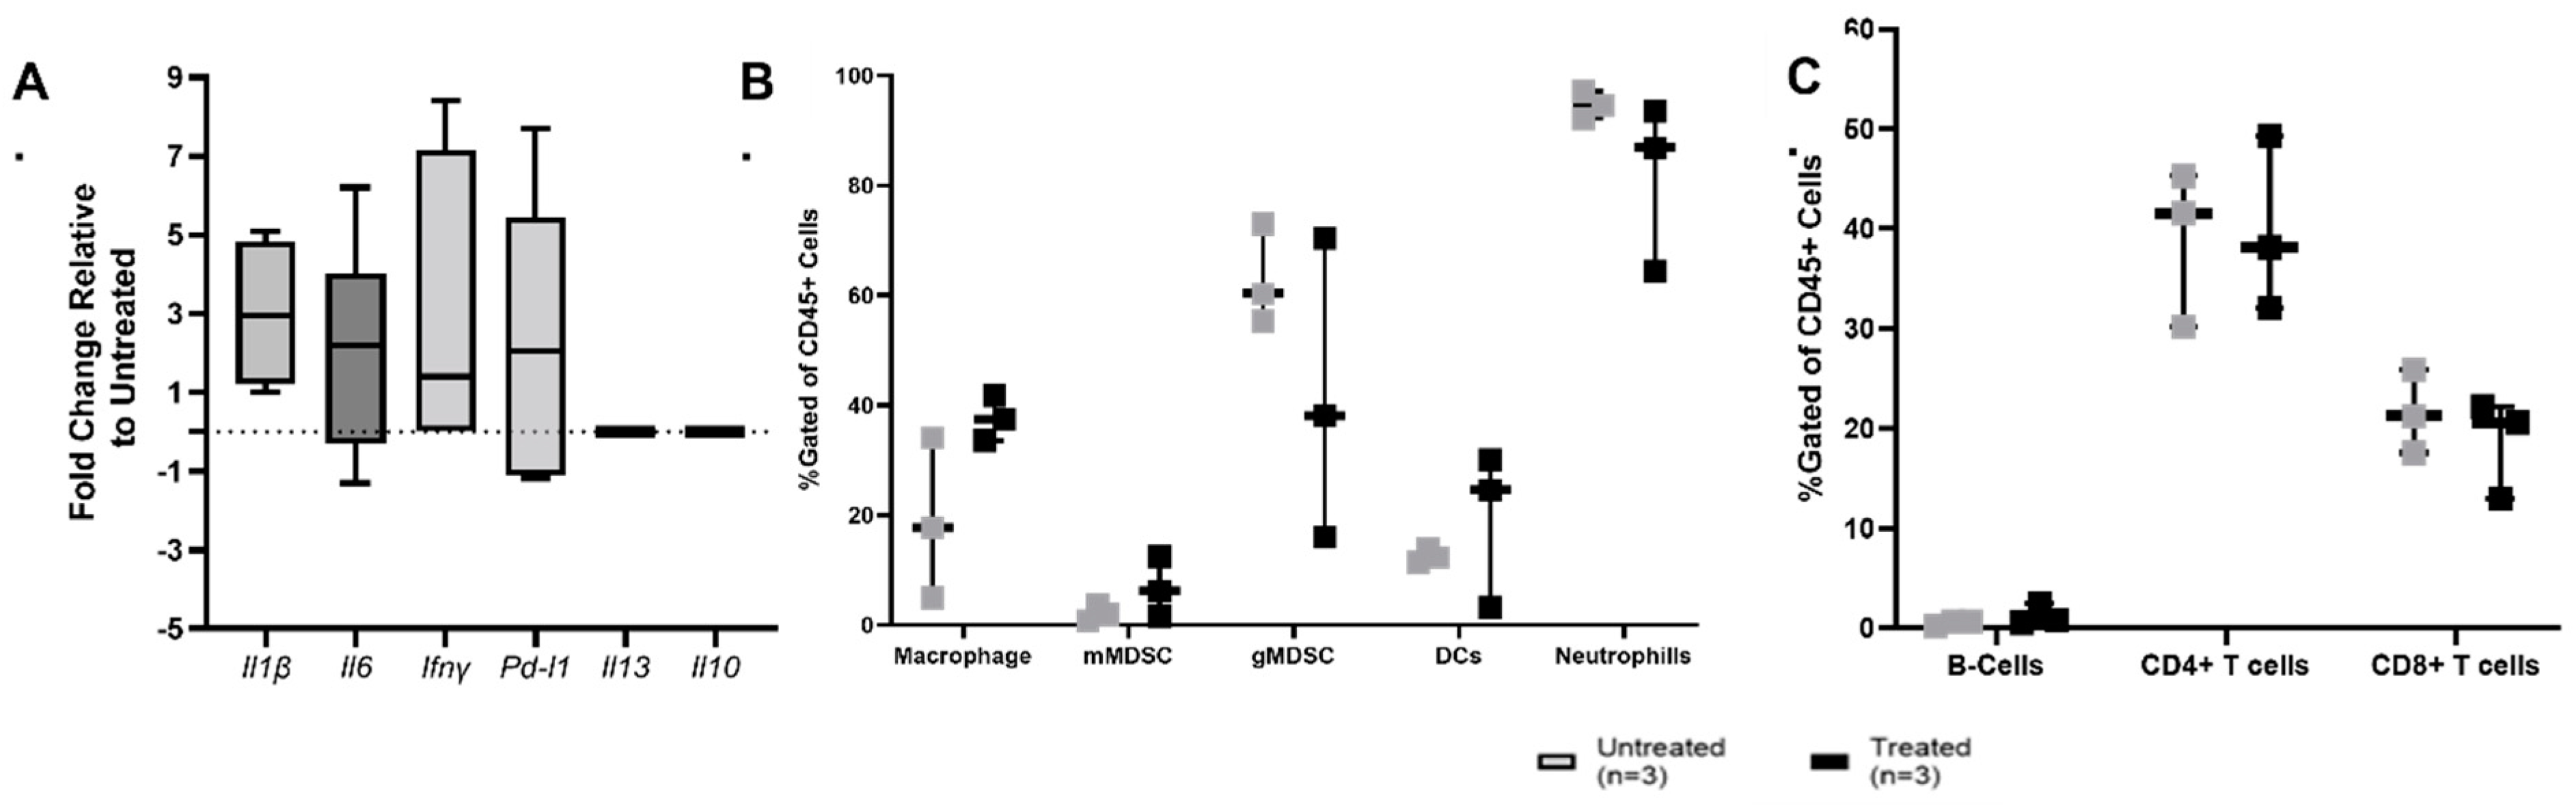

3.3. Histotripsy Ablation Induces Immune Activation within the TME